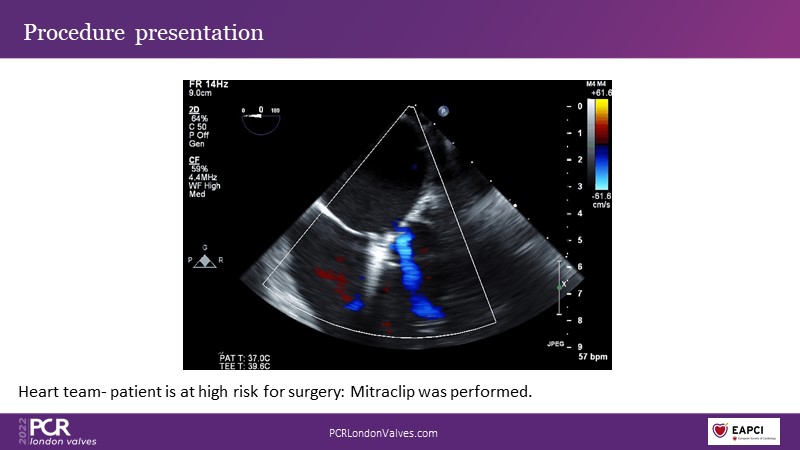

Join an advanced Heart Team in a real case discussion to understand what "mitral valve complexity" really means and to learn how to optimise selection between repair and replacement options.

- To join a real case discussion involving an advanced Heart Team

- To understand what "mitral valve complexity" really means

- To learn how to optimise selection between repair and replacement options